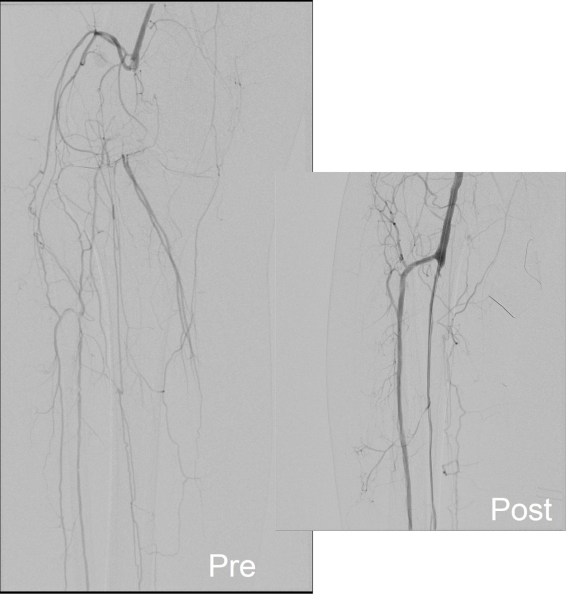

Arteriography was performed via a left common femoral access and is shown below.

The popliteal artery was occluded and there was a very small peroneal artery that continued down the leg with seeming occlusion of the anterior and posterior tibial arteries. The popliteal and anterior tibial artery were exposed through a below knee incision taking care to avoid venous injury which can be troublesome source of bleeding. The tibioperoneal trunk down to the bifurcation and origin of the peroneal artery was exposed through the same incision. And anterior tibial artery origin was controlled with a vessel loop largely out of habit although it seemed clear it was occluded, as were the proximal popliteal and tibioperoneal trunk branches. The arteriotomy was created from the tibioperoneal trunk to the popliteal artery and endarterectomy was performed from distal to proximal to create a starting point for the ring dissectors used in remote endarterectomy. The anterior tibial plaque branched off much like an external carotid artery plaque and I decided to see what would happen if I did an eversion endarterectomy. I was able to mobilize a short length of the artery and was able to pull as I endarterectomized around the plaque and it thinned very nicely and came out with a gossamer end point. More gratifyingly, the backbleeding was excellent –this was controlled with the vessel loop very nicely. The retrograde popliteal endarterectomy was performed as described in another post in another case –link. The artery was then patched and completion arteriography was performed.

What was fascinating was it seemed I had reopened not just the pop-peroneal axis but the anterior tibial artery was also open, very dramatically so. The patient also had a bounding dorsalis pedis artery pulse. She recovered and went home two days later and in three years of followup while I was still in Iowa, she remained widely patent, maintained on Coumadin anticoagulation.